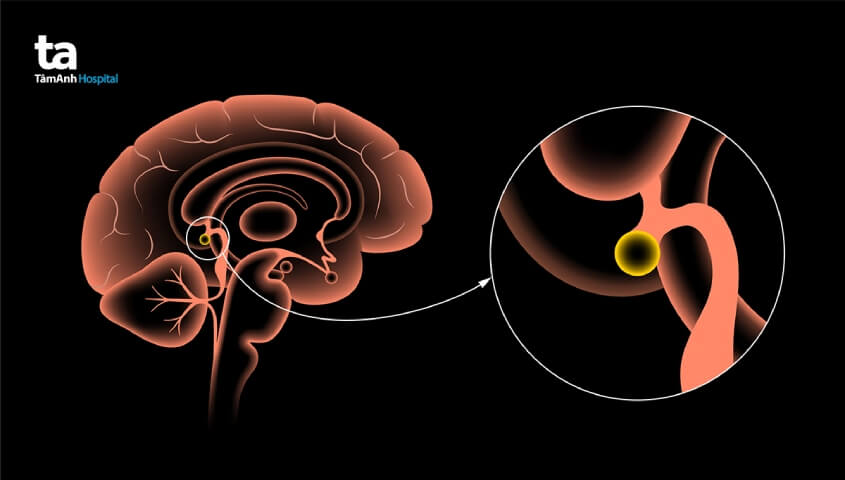

Điều trị khối u vùng tuyến tùng hoàn toàn có thể đạt được hiệu quả dứt điểm trong trường hợp người bệnh được chẩn đoán kịp thời, hướng điều trị thích hợp. U tuyến tùng là dạng khối u phát triển trong hoặc xung quanh vùng tuyến tùng của não bộ. Các khối u này sẽ được phân loại là khối u thuộc hệ thống thần kinh trung ương (CNS). Đối với các trường hợp đặc biệt chúng cũng có thể lan đến tủy sống của người bệnh.

Các khối u tuyến tùng tương đối hiếm gặp, chỉ chiếm khoảng 1% trong tỉ lệ xuất hiện các khối u não ở người lớn (thường gặp ở độ tuổi 20 – 40 tuổi) và phổ biến hơn ở trẻ em khi chiếm khoảng 3% – 11% trong tỉ lệ xuất hiện những khối u não ở trẻ. (1)

Máy móc thiết bị, phương tiện hỗ trợ quá trình phẫu thuật cũng là yếu tố quan trọng ảnh hưởng đến việc điều trị khối u tuyến tùng. Bởi vì tuyến tùng là vùng có cấu trúc giải phẫu rất phức tạp, có vị trí nằm sâu bên trong nhu mô não, xung quanh có rất nhiều mạch máu, do đó, việc phẫu thuật điều trị đòi hỏi có sự hỗ trợ tích cực từ các máy móc chuyên dụng hiện đại. Người bệnh cần tìm hiểu kỹ cơ sở vật chất tại bệnh viện và nhờ bác sĩ tư vấn thêm.